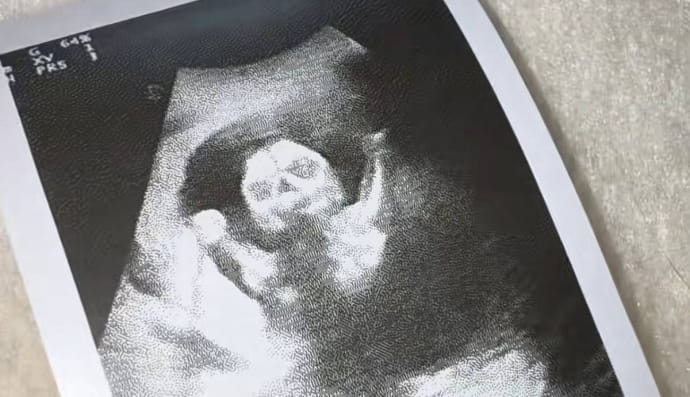

Вагітність під час вагітності: бразилійка народила дітей, зачатих у різний час (фото)

Завагітніти вдруге під час вагітності складніше, ніж виграти лотерею